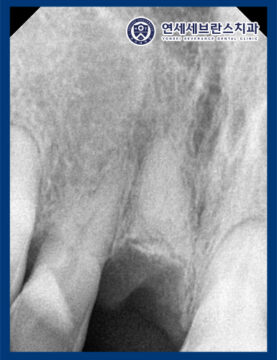

또한 CT를 촬영하여 확인해 보니,

왼쪽 위 치아는 치조골 골절을

관찰할 수 있었습니다.

발치 후 식립 전 CT를 통해

식립할 위치를 확인하고

그에 맞춰 식립을 진행하였습니다.